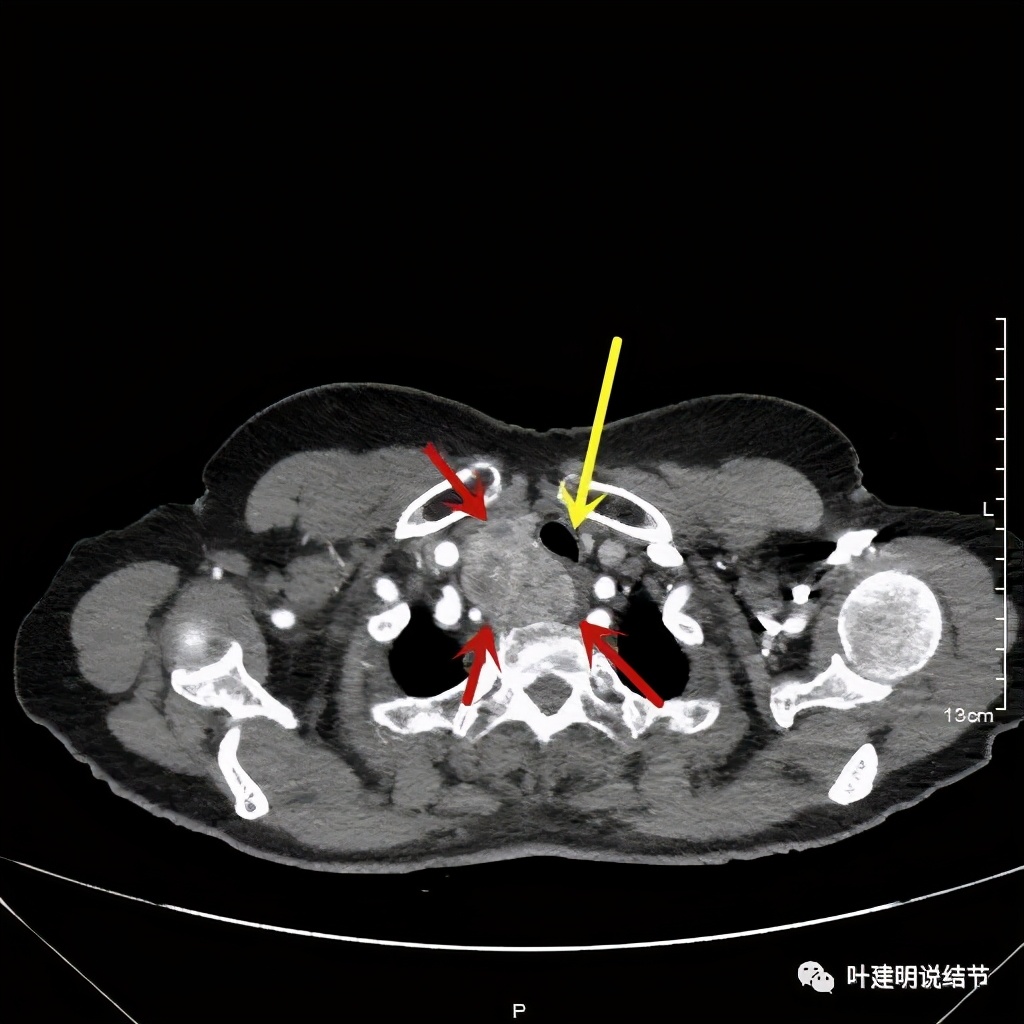

上图红色示肿瘤,黄色示气管,而且肿瘤密度不均杂乱

红色示肿瘤

上图红色示肿瘤,黄色示气管,粉色示肿瘤与气管关系密切,桔色示左无名静脉,蓝色示上腔静脉,而且肿瘤密度不均杂乱

上图红色示肿瘤,黄色示气管,桔色示左无名静脉,蓝色示上腔静脉,而且肿瘤密度不均杂乱